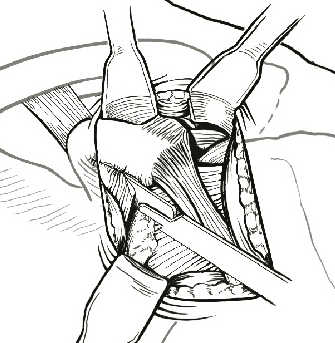

Glenoid preparation

- split subscapularis at midsubstance of muscle belly

- can perform subscapularis tenotomy

- capsulotomy - vertical or transverse

- medial glenoid retractors / Fukuda retractor over humeral head

- inferior glenoid retractor - protect AXN

- create bleeding glenoid bone with burr